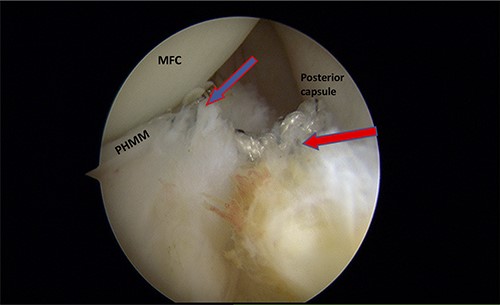

A posteromedial portal was utilized to repair both ramp tears using all-inside sutures, and curved suture hooks were inserted through the posteromedial portal. The first tear was repaired, and a non-absorbable suture was passed between the peripheral edge of the PHMM and attachment of the meniscotibial ligament (Fig. 6). The second tear was then repaired by passing the suture through the posterior capsular tissue, creating a bridge between the two tears to restore the meniscocapsular attachment (Fig. 7).

Trans-notch view of the posteromedial compartment of the left knee showing the surgical repair of the first tear. The blue arrow indicates the first lesion at the meniscosynovial junction in the red-red zone area. The red arrow shows the second tear at the meniscocapsular attachment. PHMM, posterior horn of the medial meniscus; MFC, medial femoral condyle

Trans-notch view of the postromedial compartment of the left knee showing the repair of both ramp lesion tears. The blue arrow indicates the repair of the first lesion at the meniscosynovial junction of the red-red zone area. The red arrow indicates the repaired second tear at the meniscocapsular attachment. PHMM, posterior horn of medial meniscus; MFC, medial femoral condyle